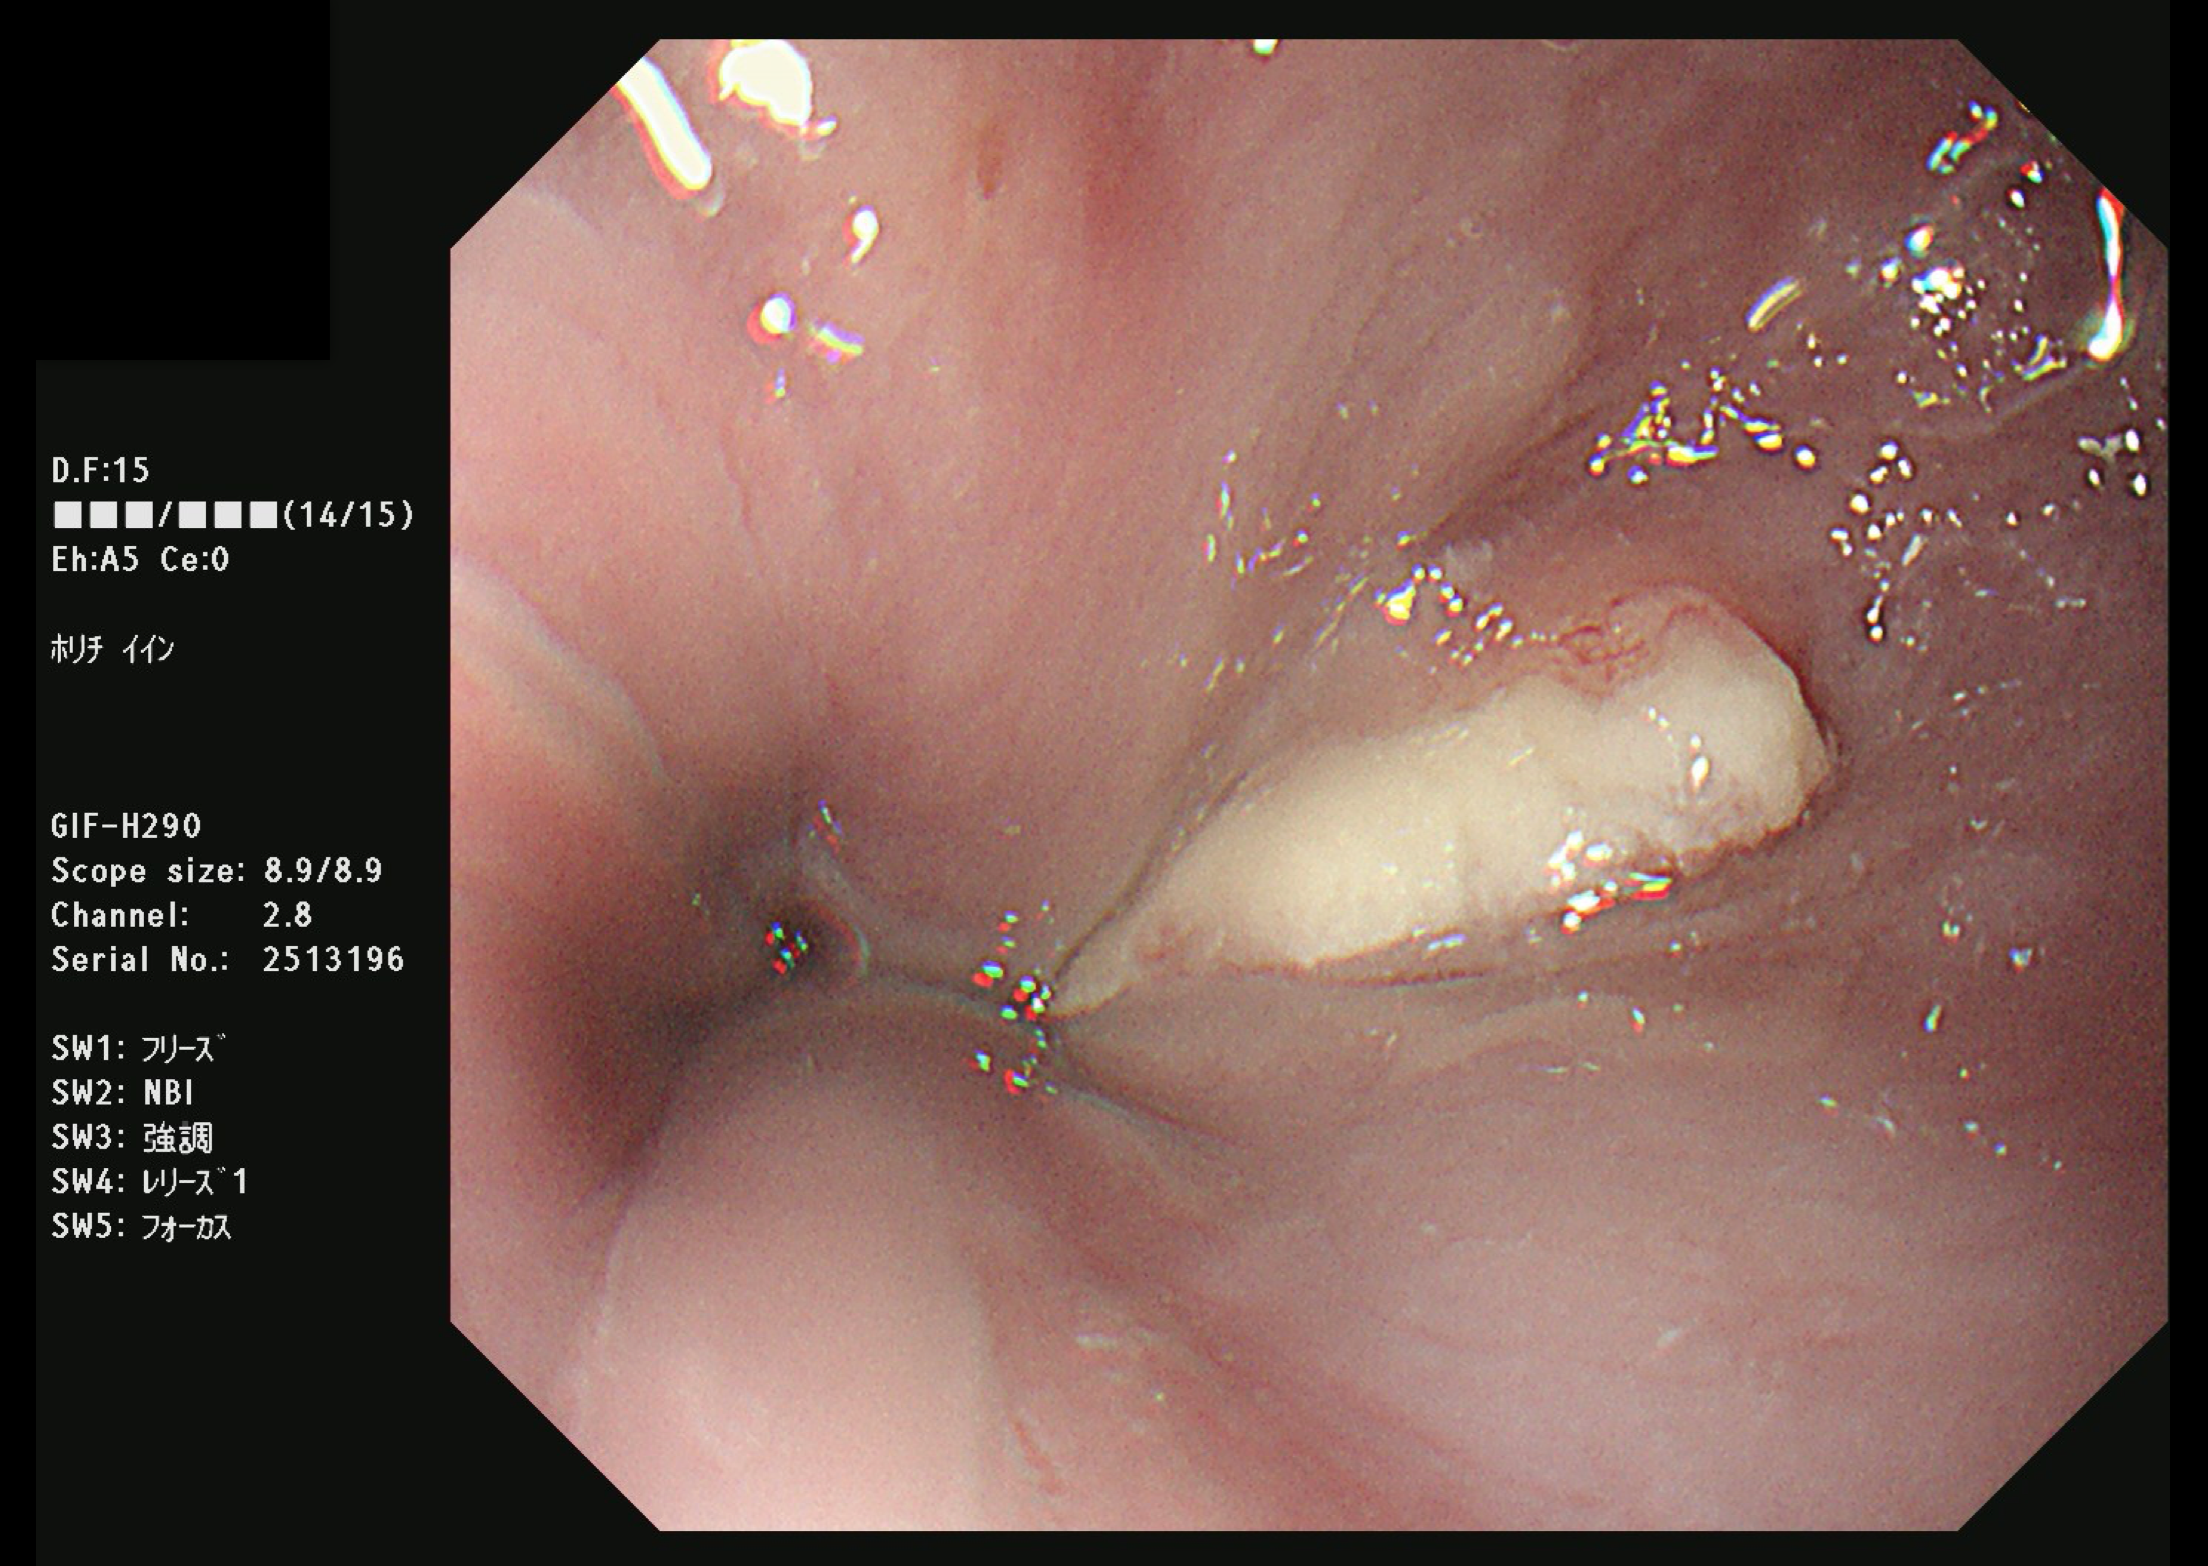

大腸がん(S状結腸癌)

大腸がん検診

大腸がん検診は検便(便中ヒトヘモグロビン検査2日法)でおこないます。

検便を2日間連続で採取し、その中のヒトヘモグロビン濃度を測定します。大腸がんも日本人に増えているがんです。

もし陽性であれば、何らかの病気がある可能性があると判断されますので、大腸の検査をおこなうことになります。

写真は過去に当院でおこなった大腸内視鏡で発見された癌ですが、現在は当院では大腸内視鏡をおこなっておりません。そのため検査をおこなう医療機関へ紹介させていただきます。